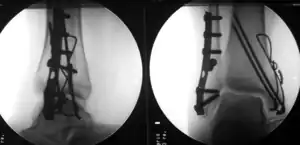

Surgically fixated bimalleolar ankle fracture

Treatment of ankle fractures is dictated by the stability of the ankle joint. Certain fractures patterns are deemed stable, and may be treated similar to ankle sprains. All other types require surgery, which is usually performed with permanently implanted metal hardware that holds the bones in place while the natural healing process occurs. A cast or splint will be required to immobilize the ankle following surgery.[1]